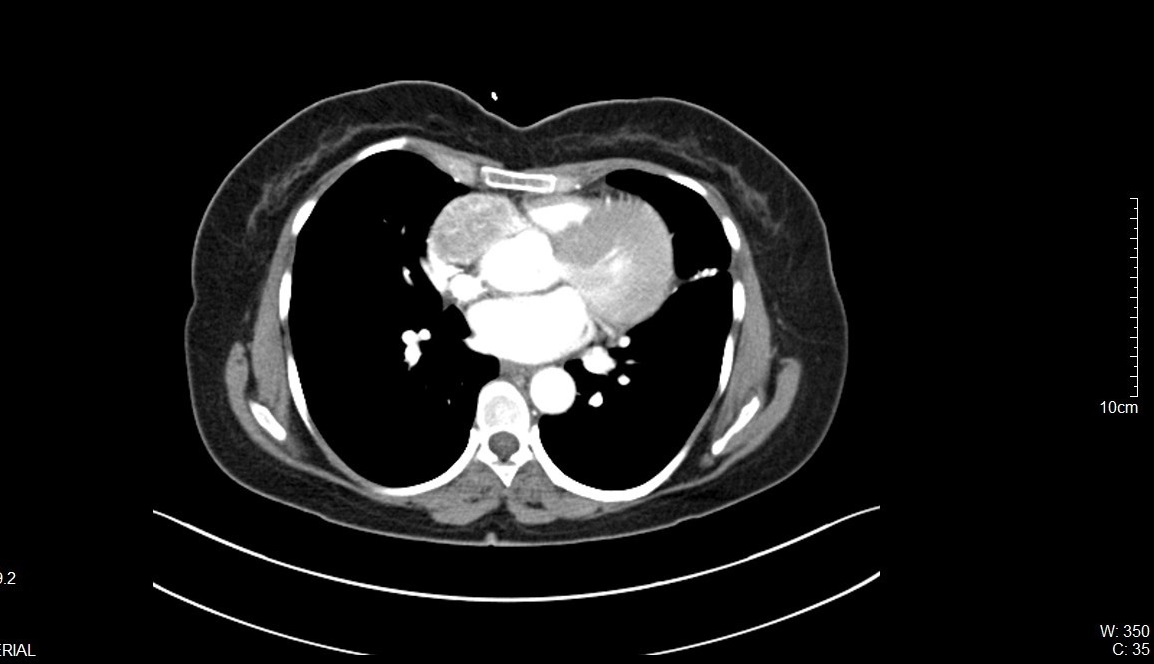

On further evaluation, the patient’s echocardiogram showed a 4.5 x 4.3 cm cystic tumor in the right atrium, hypertrophied obstructive cardiomyopathy with moderate left ventricular outflow tract obstruction, and good left ventricular function. She also underwent computed tomography (CT) and magnetic resonance imaging (MRI) of the chest, which revealed a neoplastic mass lesion, most likely right atrial myxoma.